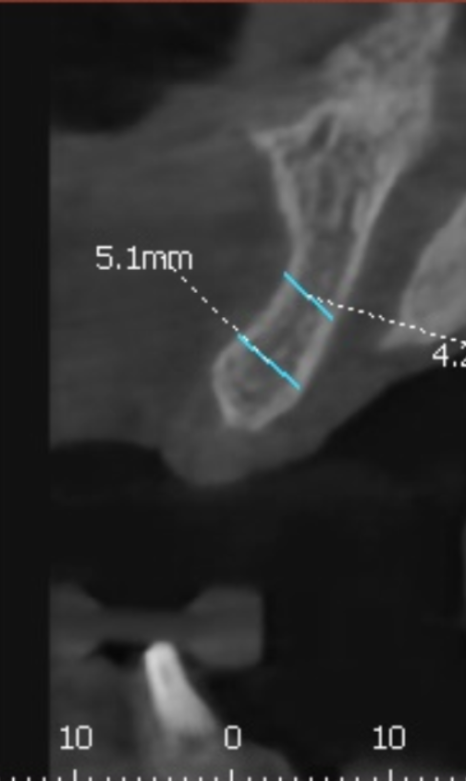

저희는 환자분들의 정확한 상태를 파악하기 위해

3D CT를 아주 꼼꼼하게 돌려보며 진단해요.

실제로 뼈이식이 꼭 필요한 부위인지,

아니면 남아있는 뼈만으로도 충분한지를

화면을 함께 보며 상세히 설명해 드립니다.

이번 환자분의 경우에도 CT를 분석해 보니

다행히 뼈의 폭이 5mm~7mm 정도로

충분히 두꺼웠습니다.

뼈의 폭이 충분하다면

굳이 뼈이식을 할 필요가 없습니다.^^

이 환자분은 뼈가 건강하셨기에

추가적인 뼈이식 없이

총 3대의 임플란트를

정확한 위치에 식립해 드렸습니다.